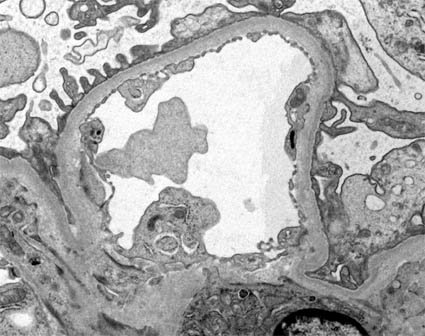

Figura 10. Electron microscopy. Normal glomerulus. In the center a mesangial area in which the nucleus of a mesangial cell (by its location) is recognized, it is surrounded by three capillaries. Note the basement membrane surrounded by podocyte processes. (Original magnification, X2.000).

Figura 10b. Electron microscopy. At higher magnification a capillary light is detailed with some blood material, fenestrated endothelium, basement membrane and podocyte processes. Note that the basement membrane is not present in the portion of the capillary that is in direct contact with the mesangium. (Original magnification, X4.000).